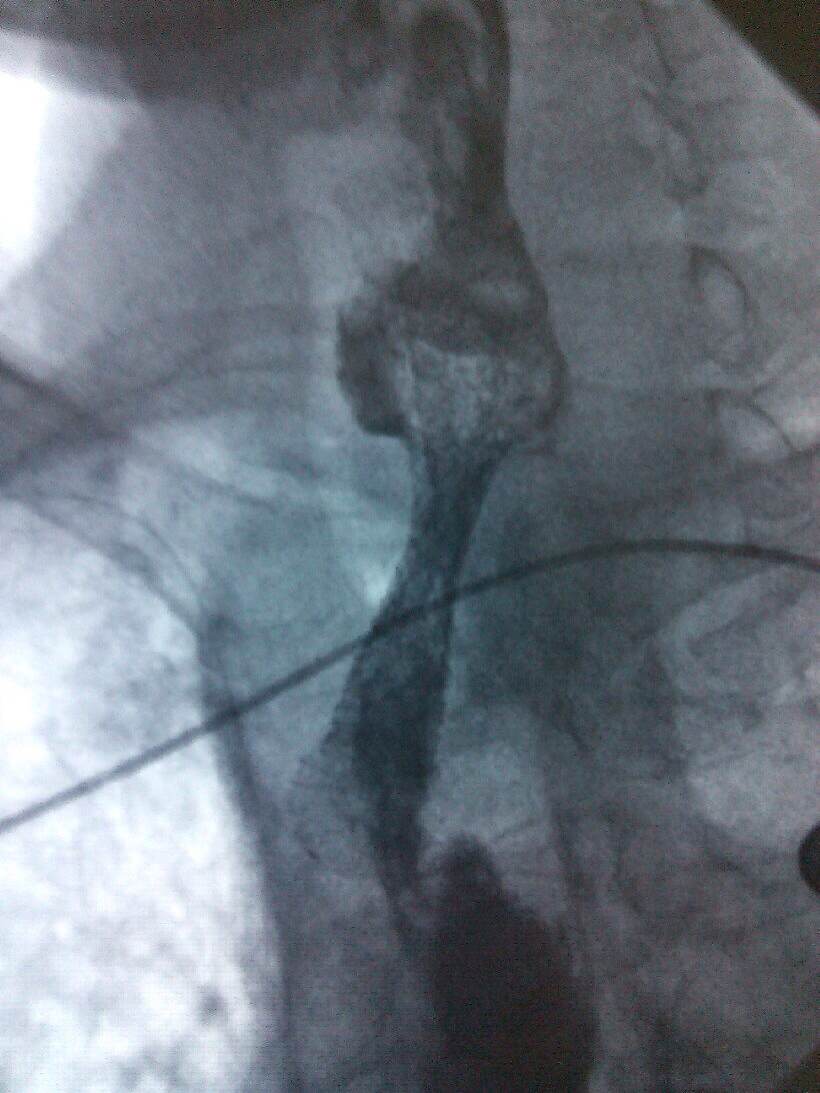

根据病人的的身体条件,无法采用手术、放疗、化疗进行治疗。肿瘤科主任、副主任医师熊小平组织医生详细分析患者的病情,找到病因所在,制定周密的治疗方案,运用食管支架植入法将食管扩张,这样既解决了患者的“吃饭”问题,又解决了分泌物排流的问题,减轻了患者的痛苦,提高了生活质量。患者及家属非常感激,多次口头表示感谢:“没想到跳蛋视频